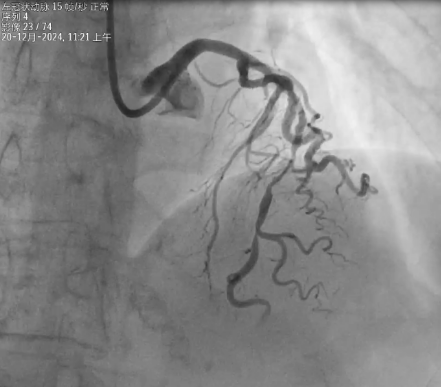

冠狀動(dòng)脈造影結(jié)果:LM:末端狹窄30%;LAD:近中段彌漫性病變并重度鈣化,中段最狹窄90%,TIMI血流III級(jí);LCX:近中段彌漫性病變,最狹窄70%,TIMI血流III級(jí);RCA:全程彌漫性病變,中段狹窄60%,TIMI血流III級(jí)。

將2.0×15mm預(yù)擴(kuò)張球囊送至LAD病變位置,由遠(yuǎn)及近分次擴(kuò)張,采用樂(lè)普2.75×12mm冠脈內(nèi)沖擊波導(dǎo)管對(duì)LAD近中段鈣化病變進(jìn)行沖擊波球囊導(dǎo)管冠脈腔內(nèi)成型預(yù)處理,先后共重復(fù)8個(gè)周期冠脈內(nèi)脈沖波治療;沖擊波球囊預(yù)處理后復(fù)查造影示LAD近中段病變較前明顯改善,鈣化環(huán)被打開(kāi),病變預(yù)處理充分,可進(jìn)一步行PCI治療,遂分別將雅培2.75×38mm.3.0×33mm冠脈支架送至LAD血管病變位置處釋放由遠(yuǎn)及近分別釋放,再分別以2.75×15mm、3.0×15mm后擴(kuò)張球囊充分?jǐn)U張支架。復(fù)查IVUS示術(shù)后支架貼壁良好,無(wú)夾層血腫形成,最小管腔面積4.81mm2,殘余狹窄57%;復(fù)查造影示LAD近中段長(zhǎng)病變消失,TIMI血流III級(jí)。